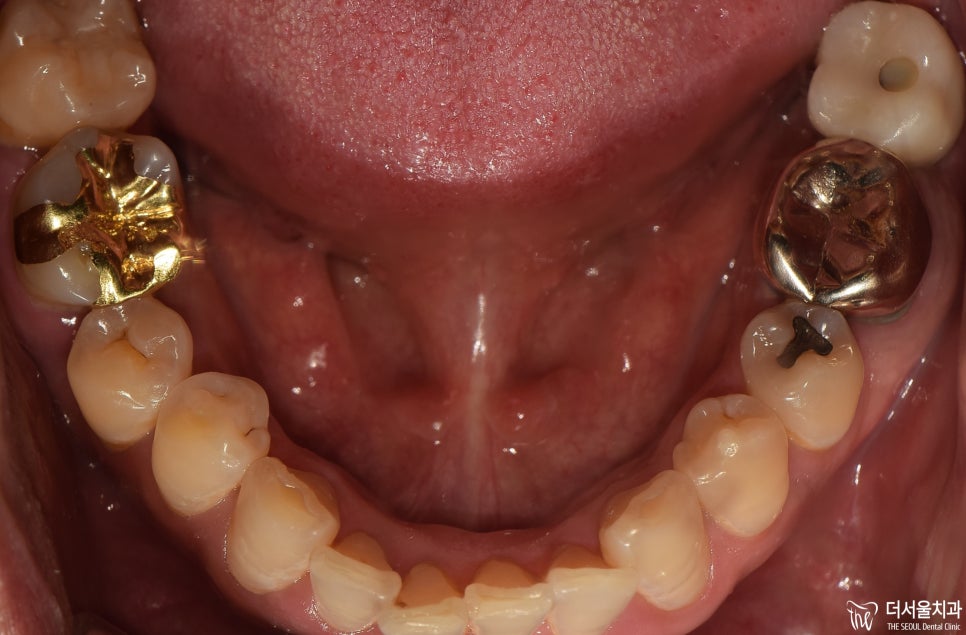

먼저 문제를 호소하는 곳을

파노라마 촬영으로 확인했습니다.

# 46, 47 뿌리 쪽으로

잇몸 염증이 발생했습니다.

골소실이 나타난 것도 볼 수 있었고,

# 46 치아는 조금 쓰러짐이 발생한 것을

확인할 수 있었습니다.

겉으로 봤을때는 멀쩡한 것처럼 보여지죠.

그런데 속은 전혀 그렇지 않았다는 사실.